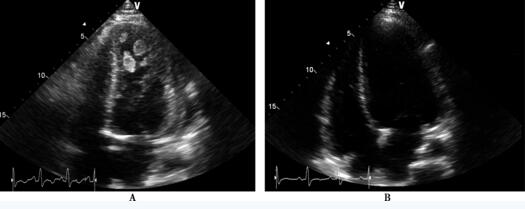

超声心动图:左心房内径40mm,左心室舒张末期内径65mm,左心室射血分数22.9%;左心室、右心室腔内探及多枚团块状回声,部分活动度较大,有蒂附着于心室壁;轻-中度二尖瓣关闭不全,轻度三尖瓣关闭不全(图77-2 A)。进一步检查胸腹部CT平扫+增强:右中肺动脉分支栓塞,伴右中肺部分梗死形成;两下肺及舌叶少许炎症;心影增大;两侧胸腔少量积液;肠系膜上动脉起始处狭窄;两侧部分肾实质低密度影,考虑梗死可能(图77-3)。

患者入院后,给予血管紧张素转换酶抑制剂、β受体阻滞剂、利尿剂等抗心力衰竭,并充分抗凝治疗 (低分子肝素与华法林重叠使用5天后,改为单用华法林,根据INR调整华法林用量,将INR控制在2.5~3.0)。1个月后,复查超声心动图:左心房内径38mm,左心室舒张末期内径68mm,左心室射血分数24.8%;左心室、右心室腔内团块状回声消失;轻-中度三尖瓣关闭不全,轻度三尖瓣关闭不全(图77-2B)。

图77-2 超声心动图 A:心尖四腔切面显示左心室腔内探及多枚带蒂的团块状回声飘动; B:抗凝治疗2周复查,心尖四腔切面显示心腔内团块状回声消失